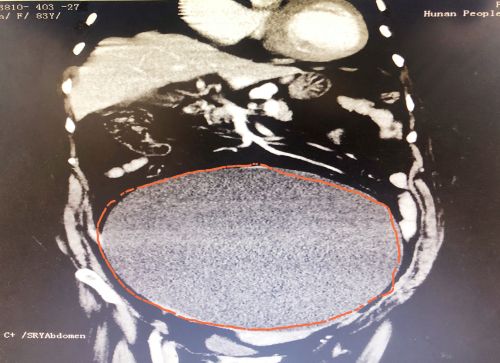

ct显示,肿瘤几乎占据老人整个盆腔和腹腔。

2021年1029日,彭娭毑住进捷克论坛 妇科病房。完善相关检查发现,巨大的肿瘤几乎占据她整个盆腔和腹腔,并且压迫肠道和膀胱,这也是老人尿频的原因。与此同时,术前血液检查发现了异常——全系细胞减少,进一步骨髓穿刺结果为:可疑B细胞淋巴瘤骨髓浸润。

经过充分讨论并做好充足的术前准备后,1112日,妇科黄薇主任团队在麻醉科、手术室的配合下,秉持无瘤操作原则,为老人施行单孔腹腔镜手术。在她肚脐上打一个小孔,缓慢引流出约4000毫升清亮的囊液。术中发现,左侧巨大的卵巢肿瘤与肠管致密大片粘连;精细分离后,顺利切除缩小的卵巢肿瘤和双侧附件,快速病检证实为“双侧卵巢浆液性囊腺瘤”。